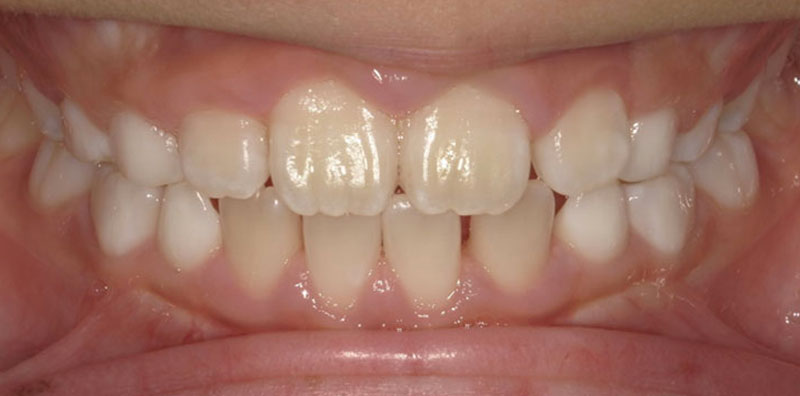

患者様は「右上2番目の歯が内側に入っていること」および「前歯の突出感(クチゴボ)」を主訴として来院されました。

本来であれば抜歯を含めた全顎矯正が望ましいケースでしたが、患者様のご希望により短期間での部分矯正を行いました。

部分矯正では上下顎前突の大きな改善は難しい旨を事前にご説明し、ご了承のうえ治療を開始しました。

治療の結果、交叉咬合(シザーズバイト)となっていた上下前歯部は、正常被蓋(上の歯が下の歯を適切に覆う状態)を獲得することができ、歯列の整った状態に仕上がりました。

患者様には「きれいに並んだ歯」をご覧いただき、大変ご満足いただけています。

| 患者様 | 10代女性 |

| 主訴 | 右上2番目の歯の内側転位 |

| 所見 | 左右2番交叉咬合、上下顎前突 |

| 治療装置 | マルチブラケット |

| 装置装着部位 | 上下3〜3の12本 |

| 治療費 | 33万円(税込) |

| 治療期間 | 約6か月(約10回通院) |